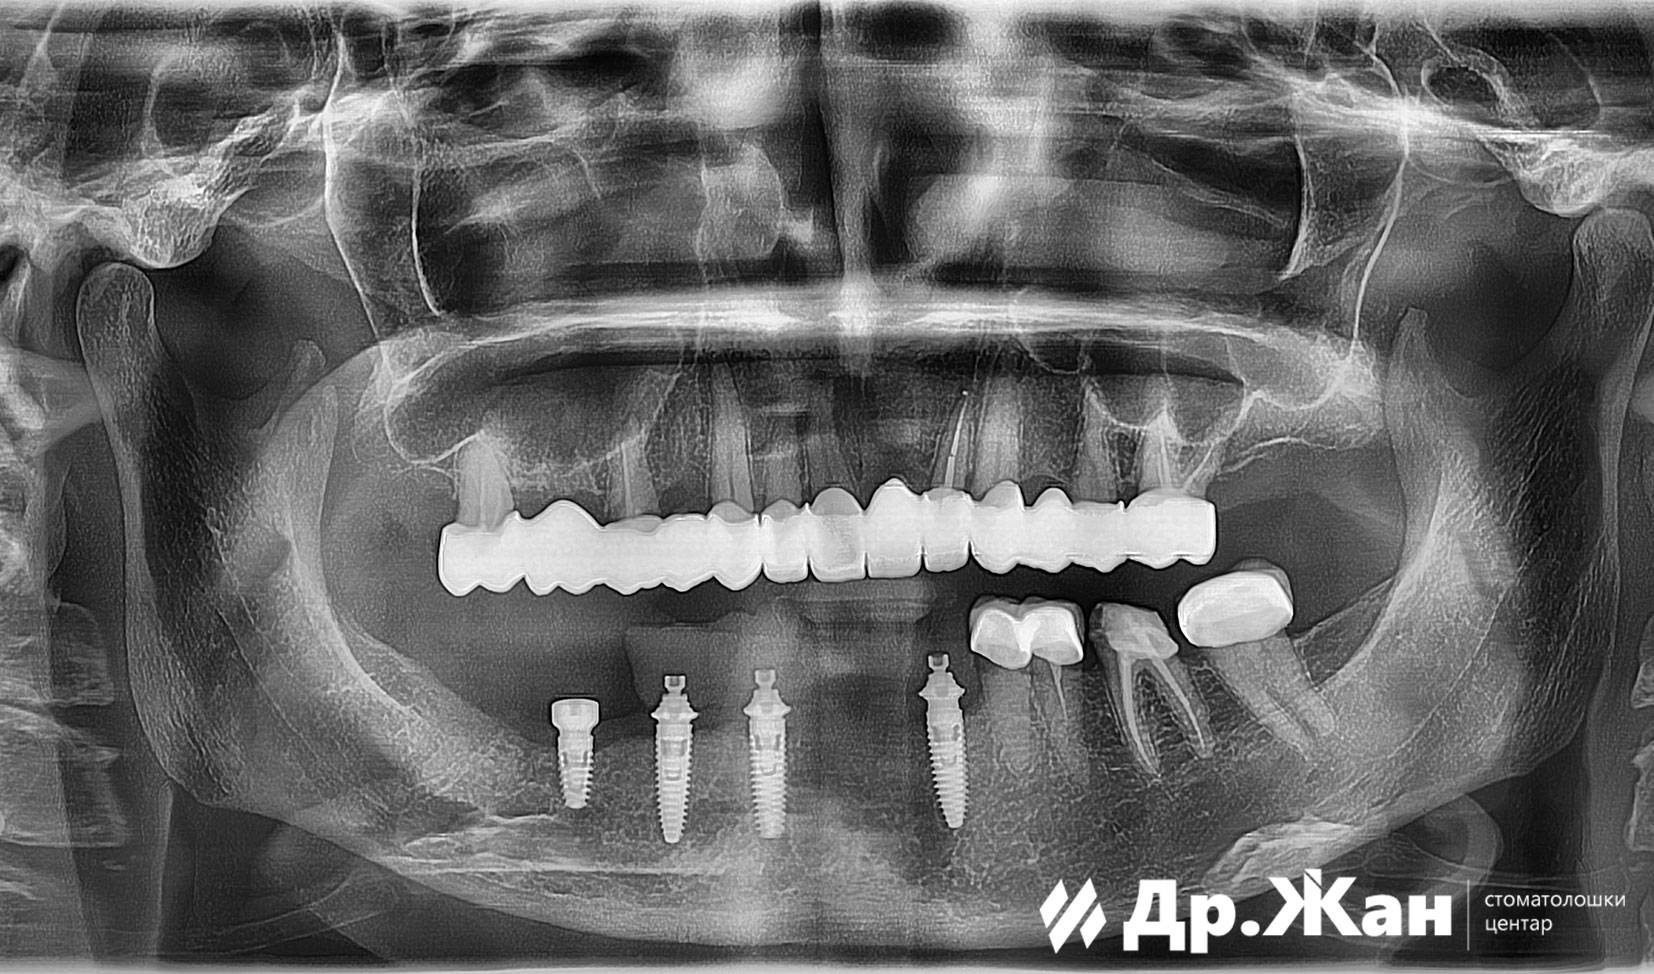

Прво поставивме 4 импланти во долната вилица и веднаш ѝ обезбедивме на пациентката фиксни привремени привремени заби. Ги оставивме имплантите да се интегрираат во коската.

ПОТОА

Во периодот на чекање ги отстранивме старите коронки во горната вилица и ги решивме сите проблеми во врска со забите и ја коригиравме линијата на непцата на пациентката. Во текот на овој период обезбедивме привремени заби. По целосното заздравување на непцата и имплантите, направивме целосна реконструкција на устата со циркониумски коронки и мостови.